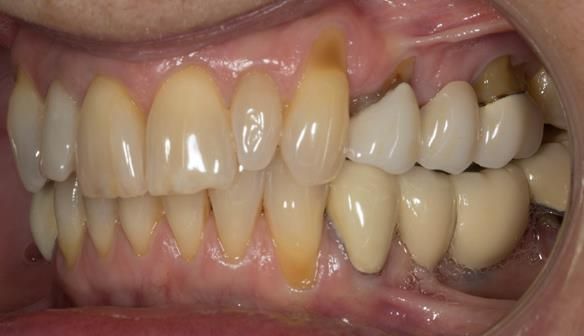

This newsletter describes in step by step detail Angela's transition through immediate partial dentures to crown supported definitive metal based dentures.

This 58 year old woman was referred to me by her general dental practitoner for treatment.

- Generalised Periodontitis; Stage 4, Grade C, Currently Unstable. Risk Factors: Type 1 diabetes. 16, 17 - hopeless prognosis. 14, 24, 26, 27, 34, 37, 44 - guarded prognosis

- Poor marginal fit and poor appearance of crowns and bridgework

- Yellowing teeth

The clinical situation and treatment process is shown in detail below with photographs. I (Finlay Sutton) provided the clinical work and Rowan Garstang provided the technical work.